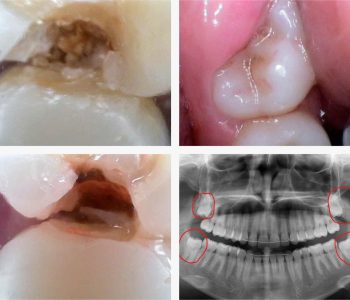

An impacted wisdom tooth can cause a number of problems that mean the tooth is best removed.

It is noteworthy that they no longer develop in a large part of the world’s population, being an echo of the times when humanity ate very tough food. Eighth molars, like other teeth, are laid in the gums from birth, but many babies are already born without them. Out placement in the lower and upper row on an already fully formed jaw often causes discomfort, inflammation during prosthetics, carries the risk of cyst formation, deformation of the dentition and many other dental problems. There is only one solution in most of these cases – removal.